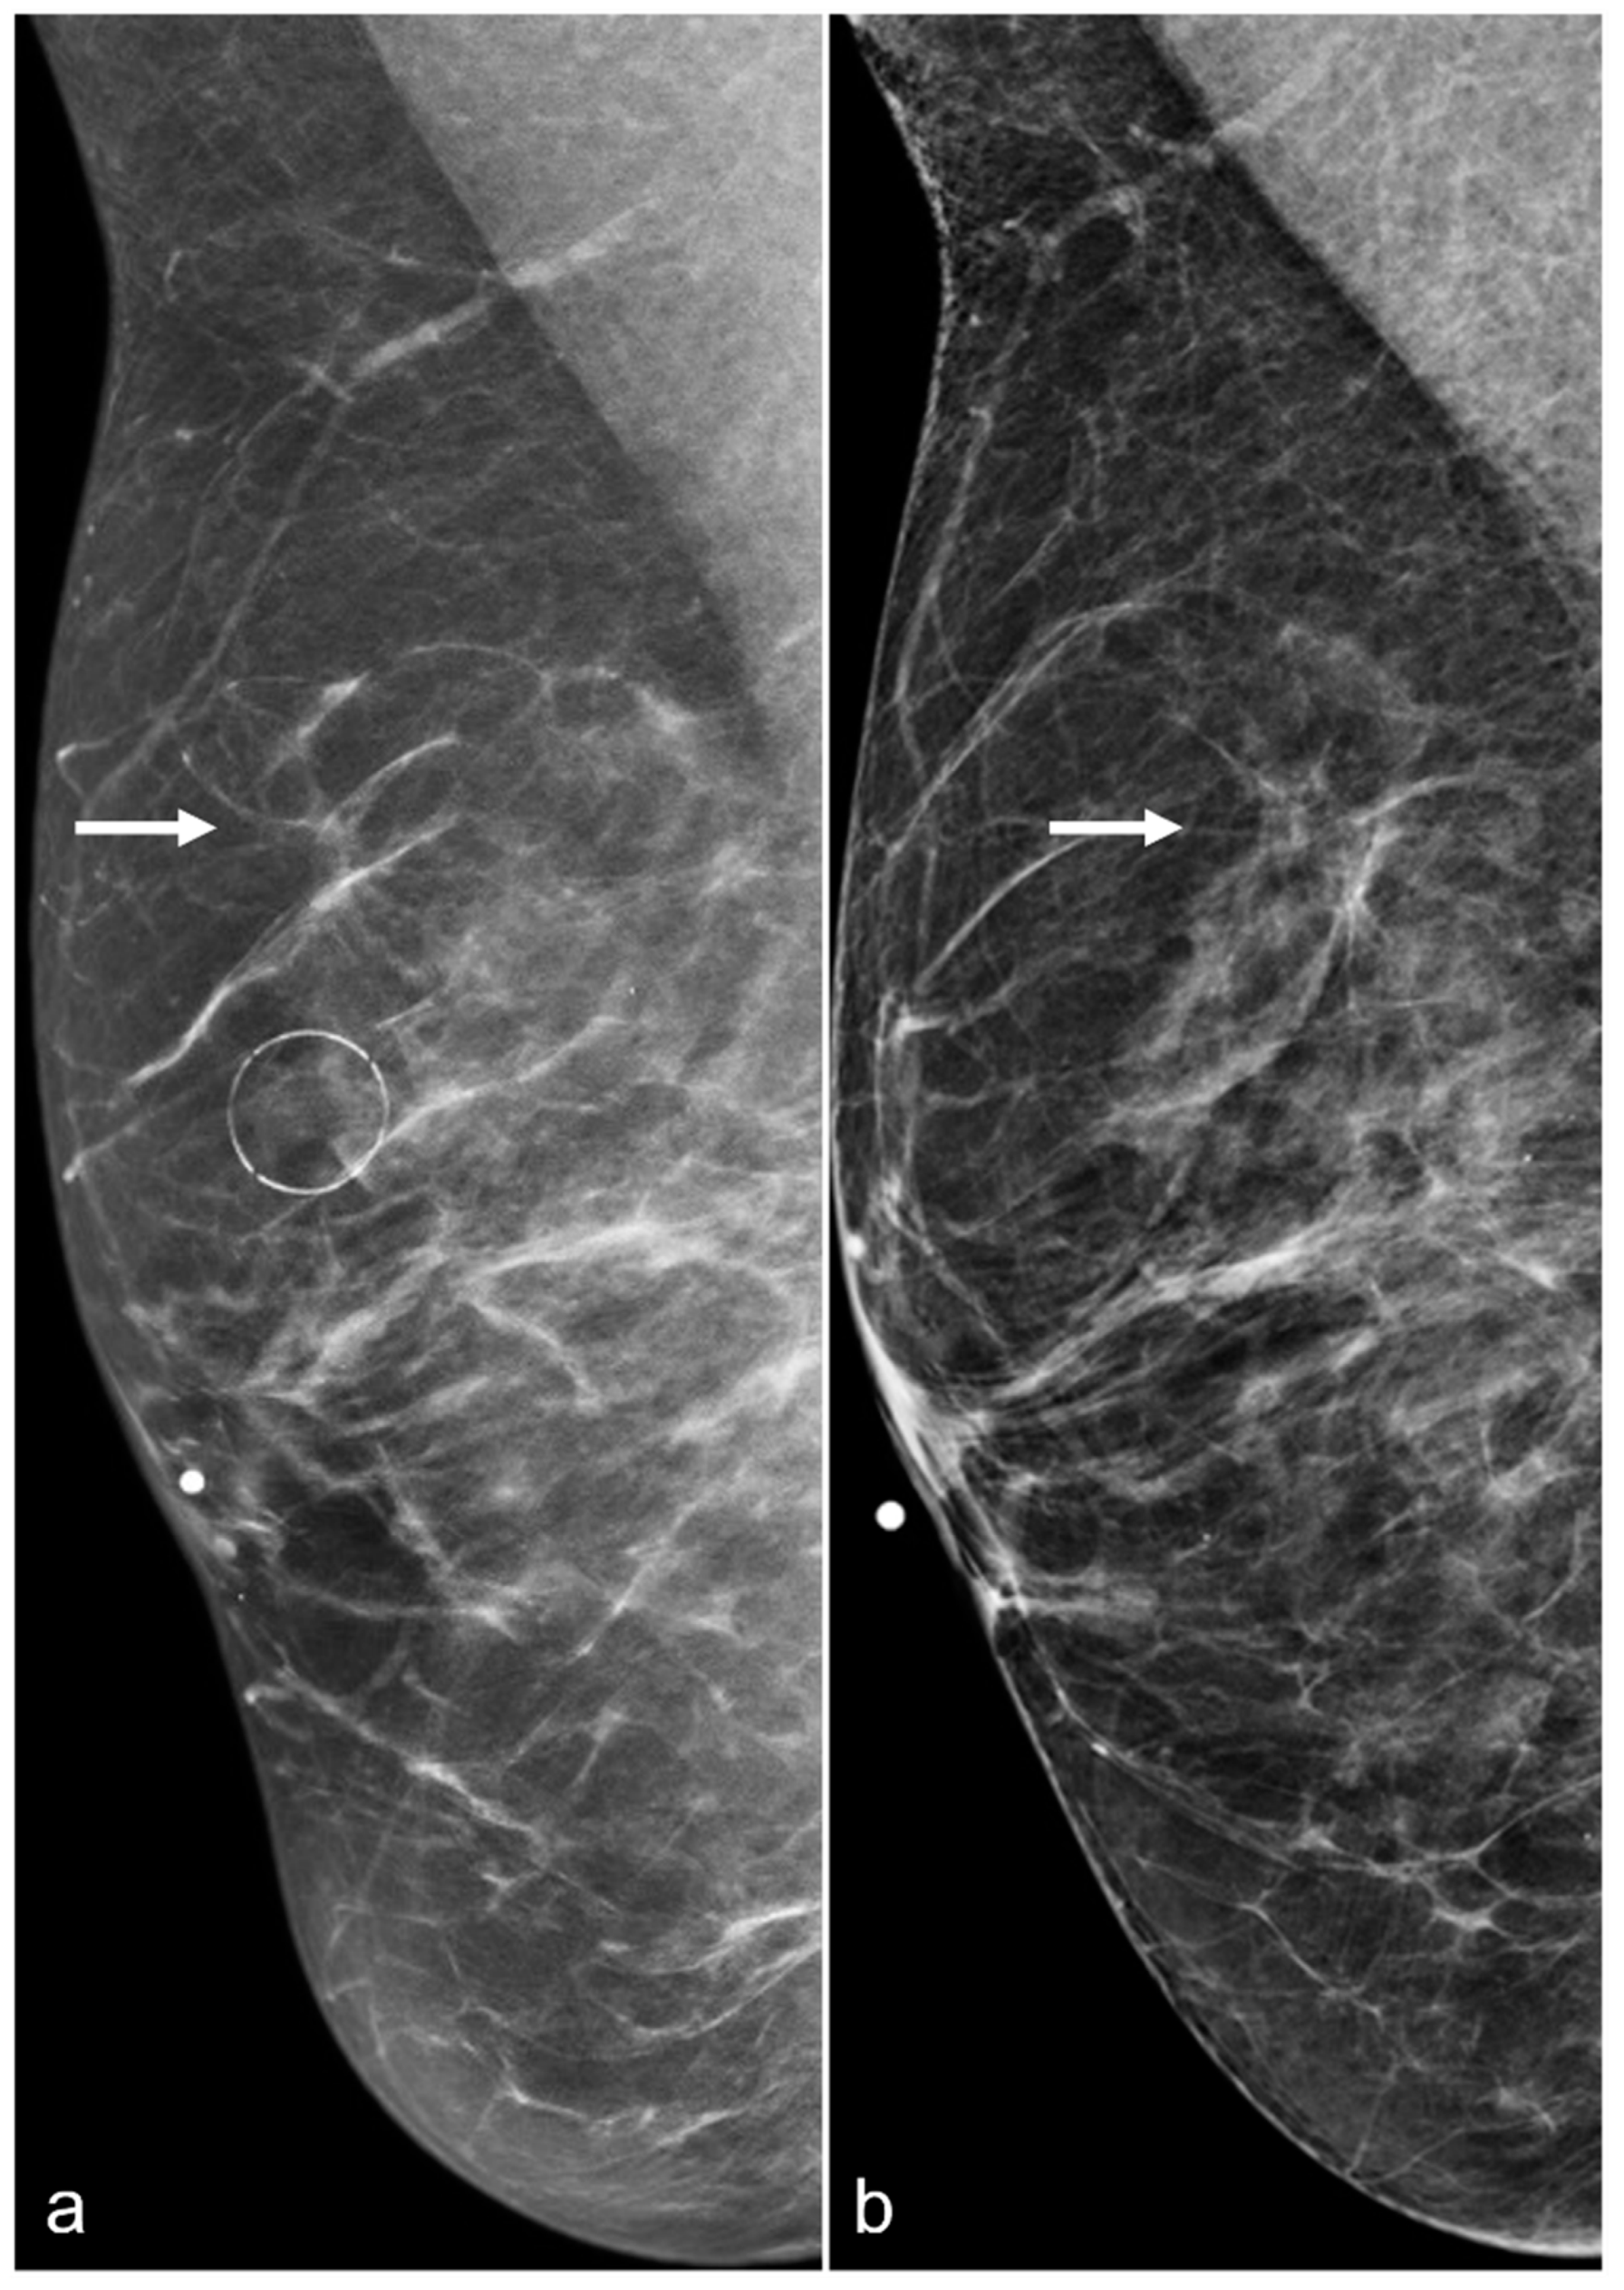

Figure 3. A 61-year-old woman had a history of subglandular silicone implants, status post BES. Surgical changes including architectural distortion (arrows) were noted in the right breast, stable for two years. ((a) Synthetic 2D MLO view from 2019; (b) 2D MLO view from 2021). The findings were consistent with post-BES change.